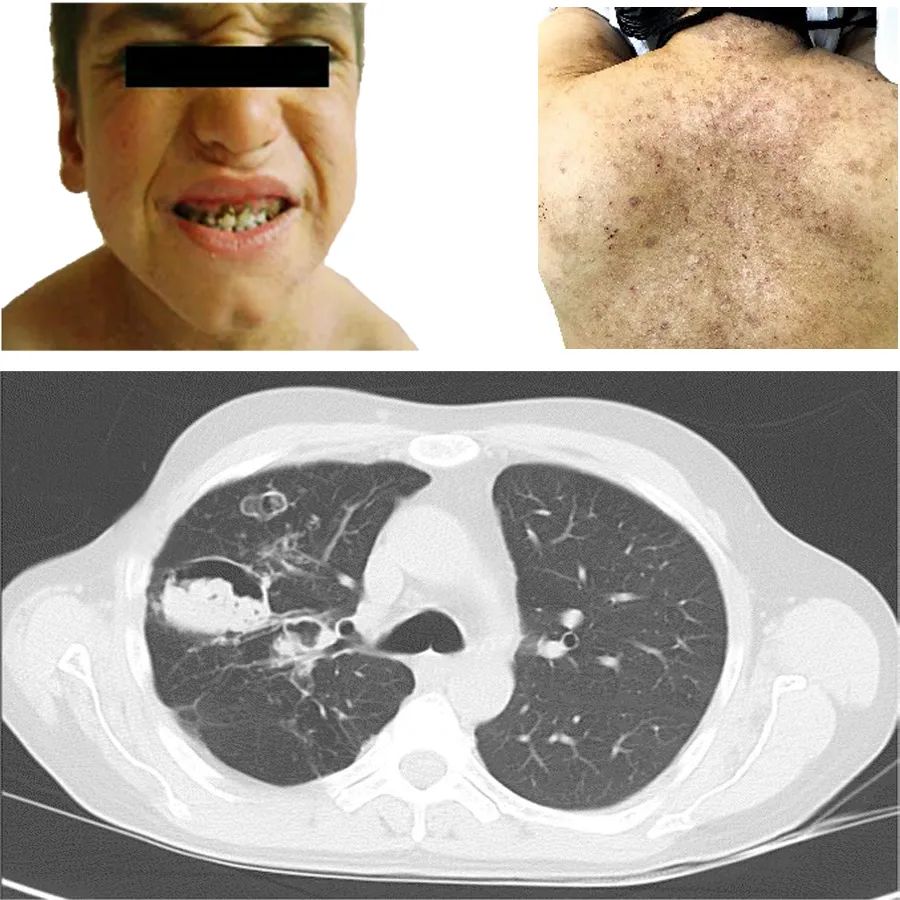

患者,男,15 岁。因躯干和四肢反复出现红斑、丘疹伴瘙痒15 年来诊。患者出生后不久,躯干和四肢反复无规律性出现数个米粒大小的红斑、丘疹,可自行消退,未进行治疗。患者1 岁零2 个月龄起,皮损数量增多、累及面积扩大,伴有明显瘙痒。患者3 岁后,反复出现咳嗽、咳痰,多次诊断为肺炎。近3 个月以来,患者皮损增多,瘙痒剧烈,再次出现刺激性干咳和咽痛。

既往于三年前因肺大疱,行胸腔镜左肺大疱切除术(当时就医时的肺CT如图)。

查体:发育一般,智力中等偏差。营养良好,神志清楚,浅表淋巴结未触及增大。粗糙面容,双眼距增宽,上颌双侧第2 乳侧切牙滞留,恒牙发育迟缓(图)。双肺呼吸音粗,右肋缘可见一长约25 cm 术后瘢痕。

皮肤科情况:躯干、四肢皮肤粗糙,大面积分布红色丘疹及斑片,表面脱屑,周围大量色素沉着斑(图)。